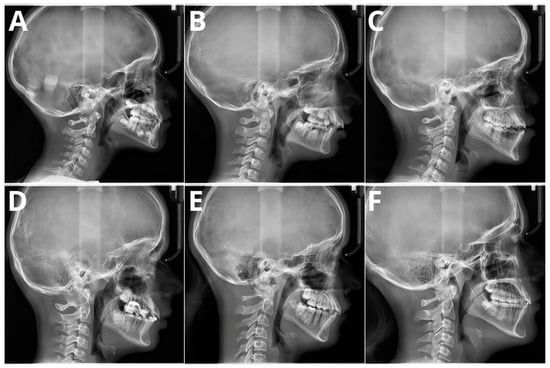

The significant problem associated with CVM evaluation is high inter- and intra-rater variability. A recent paper by Shoretsaniti et al. [] evaluated the reproducibility and efficiency of CVM assessment. The study included evaluations by six experts in radiology and orthodontics. The intra-rater reliability ranged from 77.0% to 87.3%, meaning that up to 1/4 of the diagnoses of CVM stage were changed. The results of the inter-rater agreement were even worse, with an absolute agreement calculated at 42.8%. The study also showed the lowest reproducibility for stage 3, a crucial stage that marks the beginning of pubertal growth. These results align with other studies that show significant discrepancies in CVM assessment [,,]. Such low scores of both inter- and intra-rater reproducibility indicate that the assessment of CVM stage is biased due to high variability among raters. Therefore, the results of studies showing more than 90% AI accuracy in CVM assessment should be considered very optimistic. It should be emphasized that individual errors and inconsistencies by raters assessing the CVM stage in the training sample significantly impact the learning process of the applied AI model. However, as stated in a Nature paper by Topol [], AI will likely boost human performance and accelerate decision-making in currently problematic tasks. Figure 4 presents samples of all six stages verified according to the method by Bacetti et al. [].

Figure 4.

Six maturation stages according to the method by Bacetti et al. (A) stage 1, 7 years old female; (B) stage 2, 9 years old female; (C) stage 3, 11 years old male; (D) stage 4, 12 years old male; (E) stage 5, 13 years old female; (F) stage 6, 13 years old female. Population of single, private orthodontic center, rater—orthodontist with 11 years of experience.